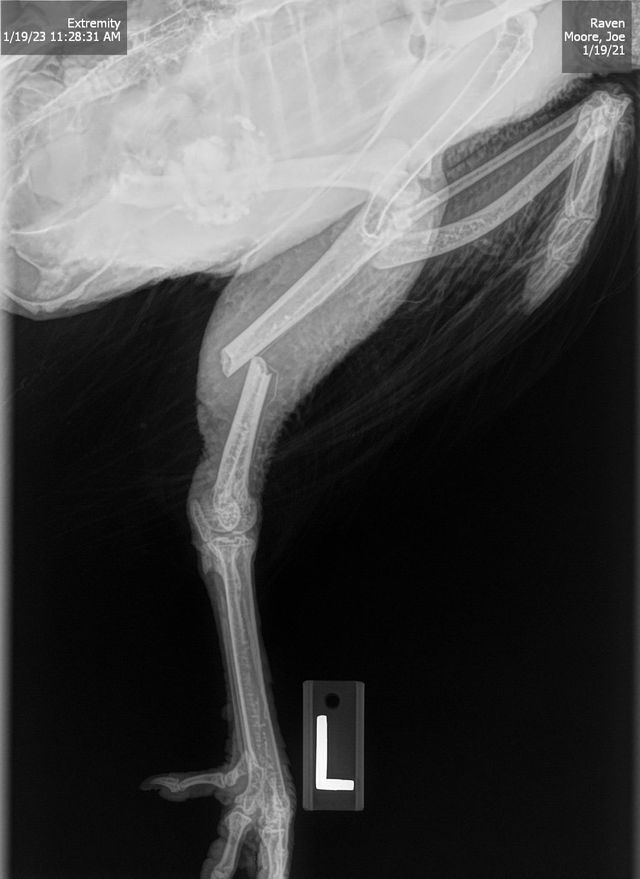

Day 2: Our veterinarian, Dr. Jammie VerGiesen, saw Raven that morning and did a radiograph with indicated “a simple comminuted, closed transverse fracture at the distal metaphysis of the left tibiotarsus”. In other words, a clean break in her upper leg. He gave us options on care, which included pinning the leg, or amputation. It was highly unlikely this would heal on its own, especially being with the rest of the flock. Though the cost estimate was much higher than we wanted to spend, curiosity got the best of us, and with an opportunity for our daughter to be a part of the process (everything except the surgery) and for her to handle the aftercare, we decided to have the leg pinned.

The vet technician plucked feathers off Raven’s leg and we were given an estimated time of 25-30 minutes for the surgery. It took an hour, as Dr. Jammie had to struggle with getting the two parts of the bone lined up properly and then pinned the leg with an external fixator device. Raven came out of surgery drooling a little and groggy, but traveled home well.